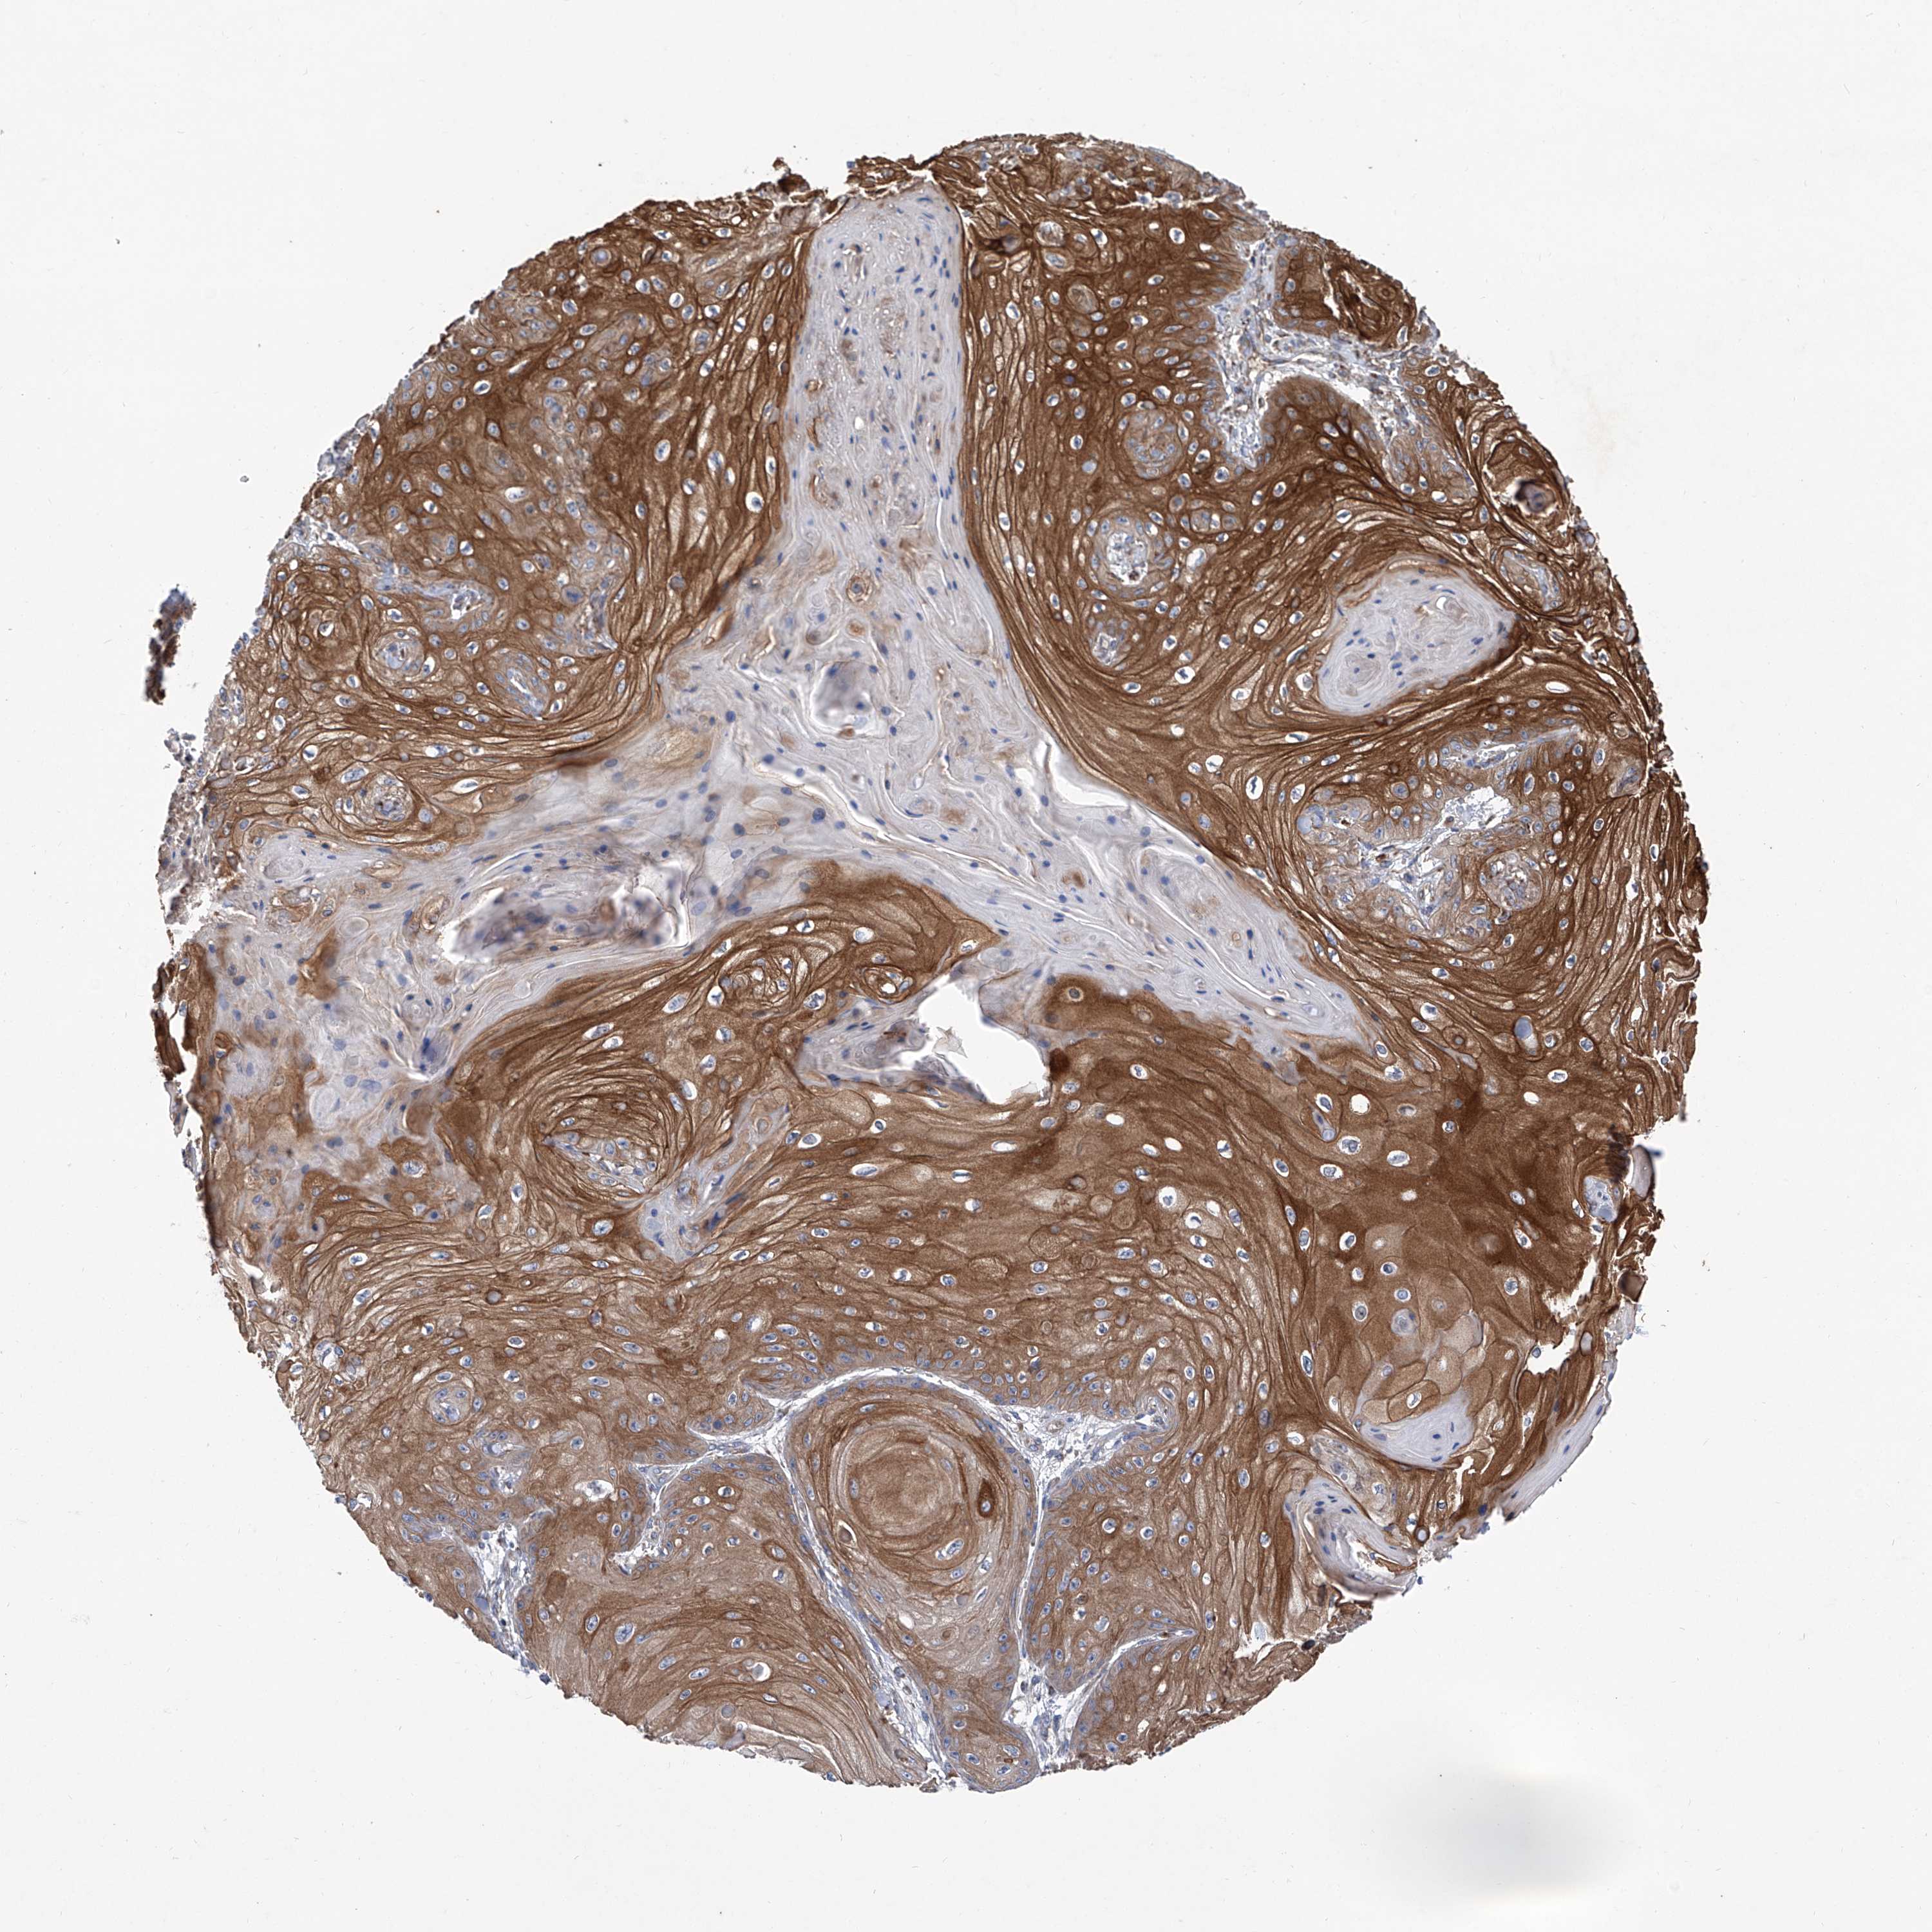

SKIN CANCER - Protein expressioni

A mouse-over function shows sample information and annotation data. Click on an image to view it in a full screen mode. Samples can be filtered based on level of antibody staining by selecting one or several of the following categories: high, medium, low and not detected. The assay and annotation is described here.

Each image is clickable and will lead to virtual microscopy that enables deeper exploration of all samples and also displays staining intensity scores, fraction scores and subcellular localization as well as patient and tissue information for each sample.

Antibody HPA031608

Antibody HPA031609

Antibody HPA031610

Staining

High

Medium

Low

Not detected

Intensity

Strong

Moderate

Weak

Negative

Quantity

>75%

75%-25%

<25%

None

Location

Nuclear

Cytoplasmic/membranous

Cytoplasmic/membranous,nuclear

Basal cell carcinoma